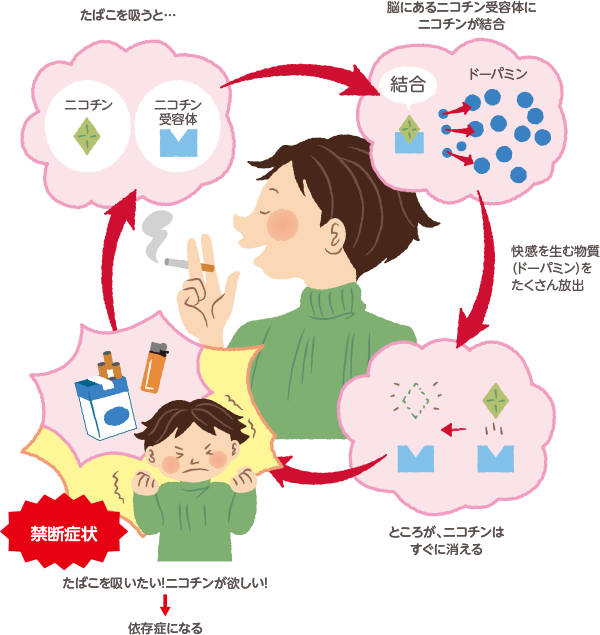

禁煙の医学 禁煙は愛 禁煙推進webサイト

禁煙教育 の部屋へようこそ